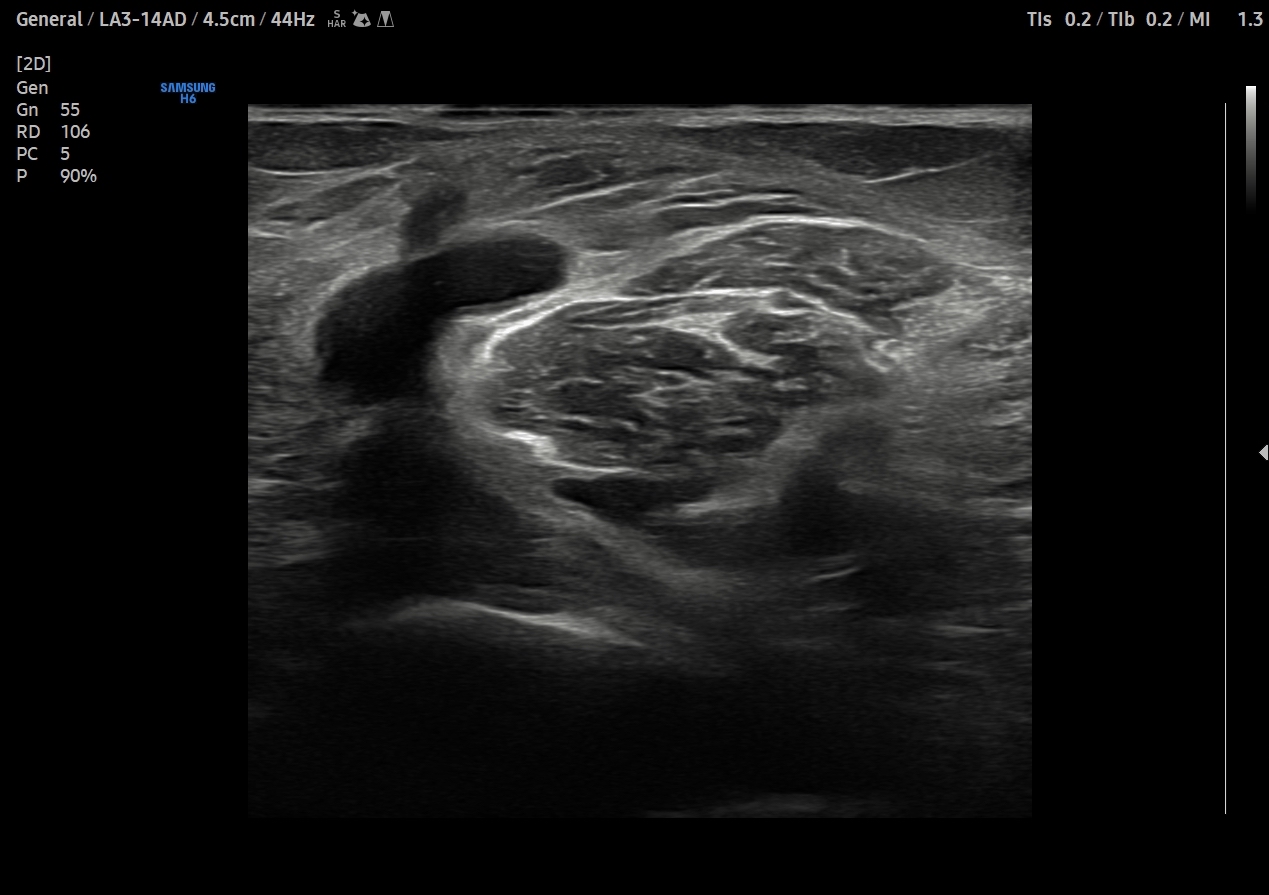

Se explora cara anterior, lateral y medial de rodilla sin hallazgos significativos. En cara posterior se explora el hueco poplíteo donde se visualiza en corte transversal una estructura hipoecoica con la base, el cuello entre el tendón del semimembranoso y el tendón de la cabeza medial del gemelo interno y el cuerpo. Sin signos de complicación. Permeabilidad del sistema venoso profundo.

Quiste de Baker.

En 15 días vemos de nuevo con mejoría de la sintomatología. Repetimos ecografía viendo menor cantidad de líquido por lo que mantenemos actitud.